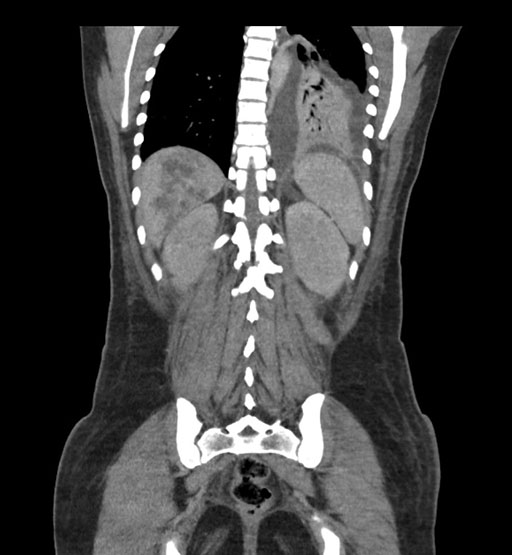

Coronal Arterial